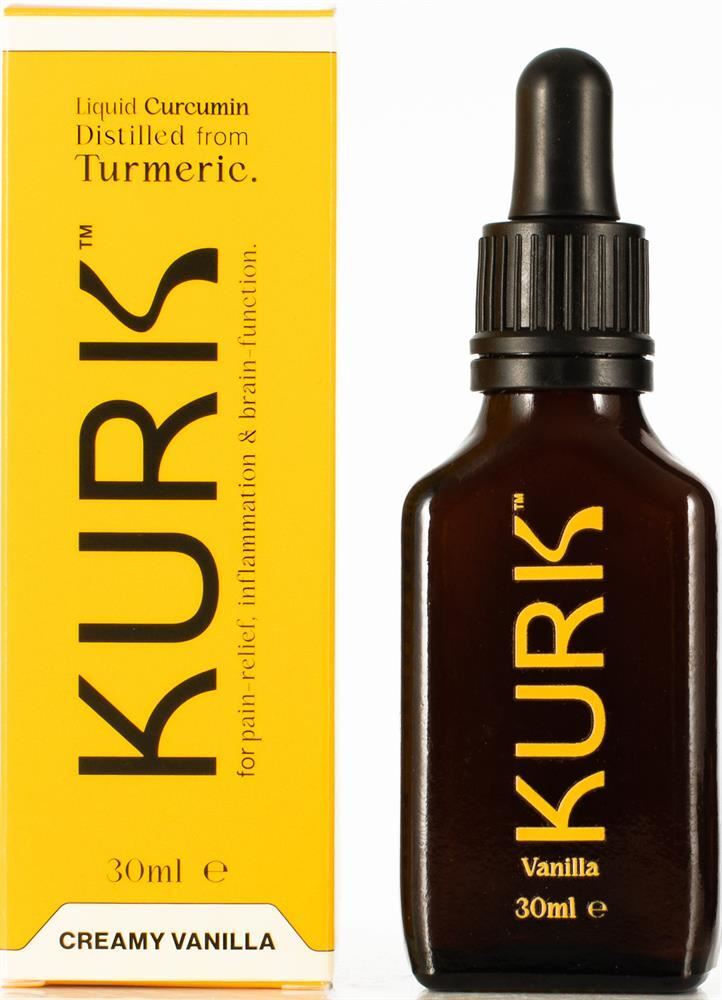

Curcumin (Active Compound in Turmeric)

The challenge with curcumin has always been bioavailability — it’s poorly absorbed on its own. Kurk’s Curcumin addresses this through formulation strategies designed to improve absorption and utilisation.

Technical Summary

This formula works because it:

Supports inflammatory balance rather than blocking inflammation

Uses a high-absorption curcumin form

Targets joint, muscle, and connective tissue stress

Fits long-term health and recovery strategies